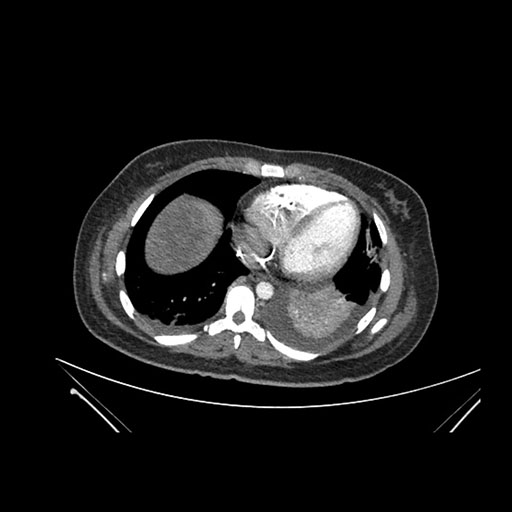

Axial Arterial